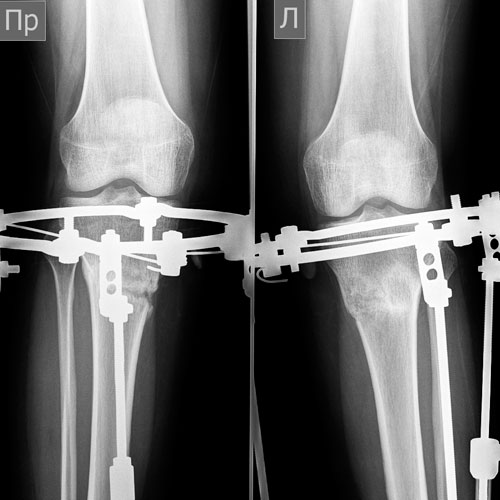

Дата операции 11.03.2014г.

Дата снятия аппаратов 10.06.2014г.

Срок лечения 3 месяца.